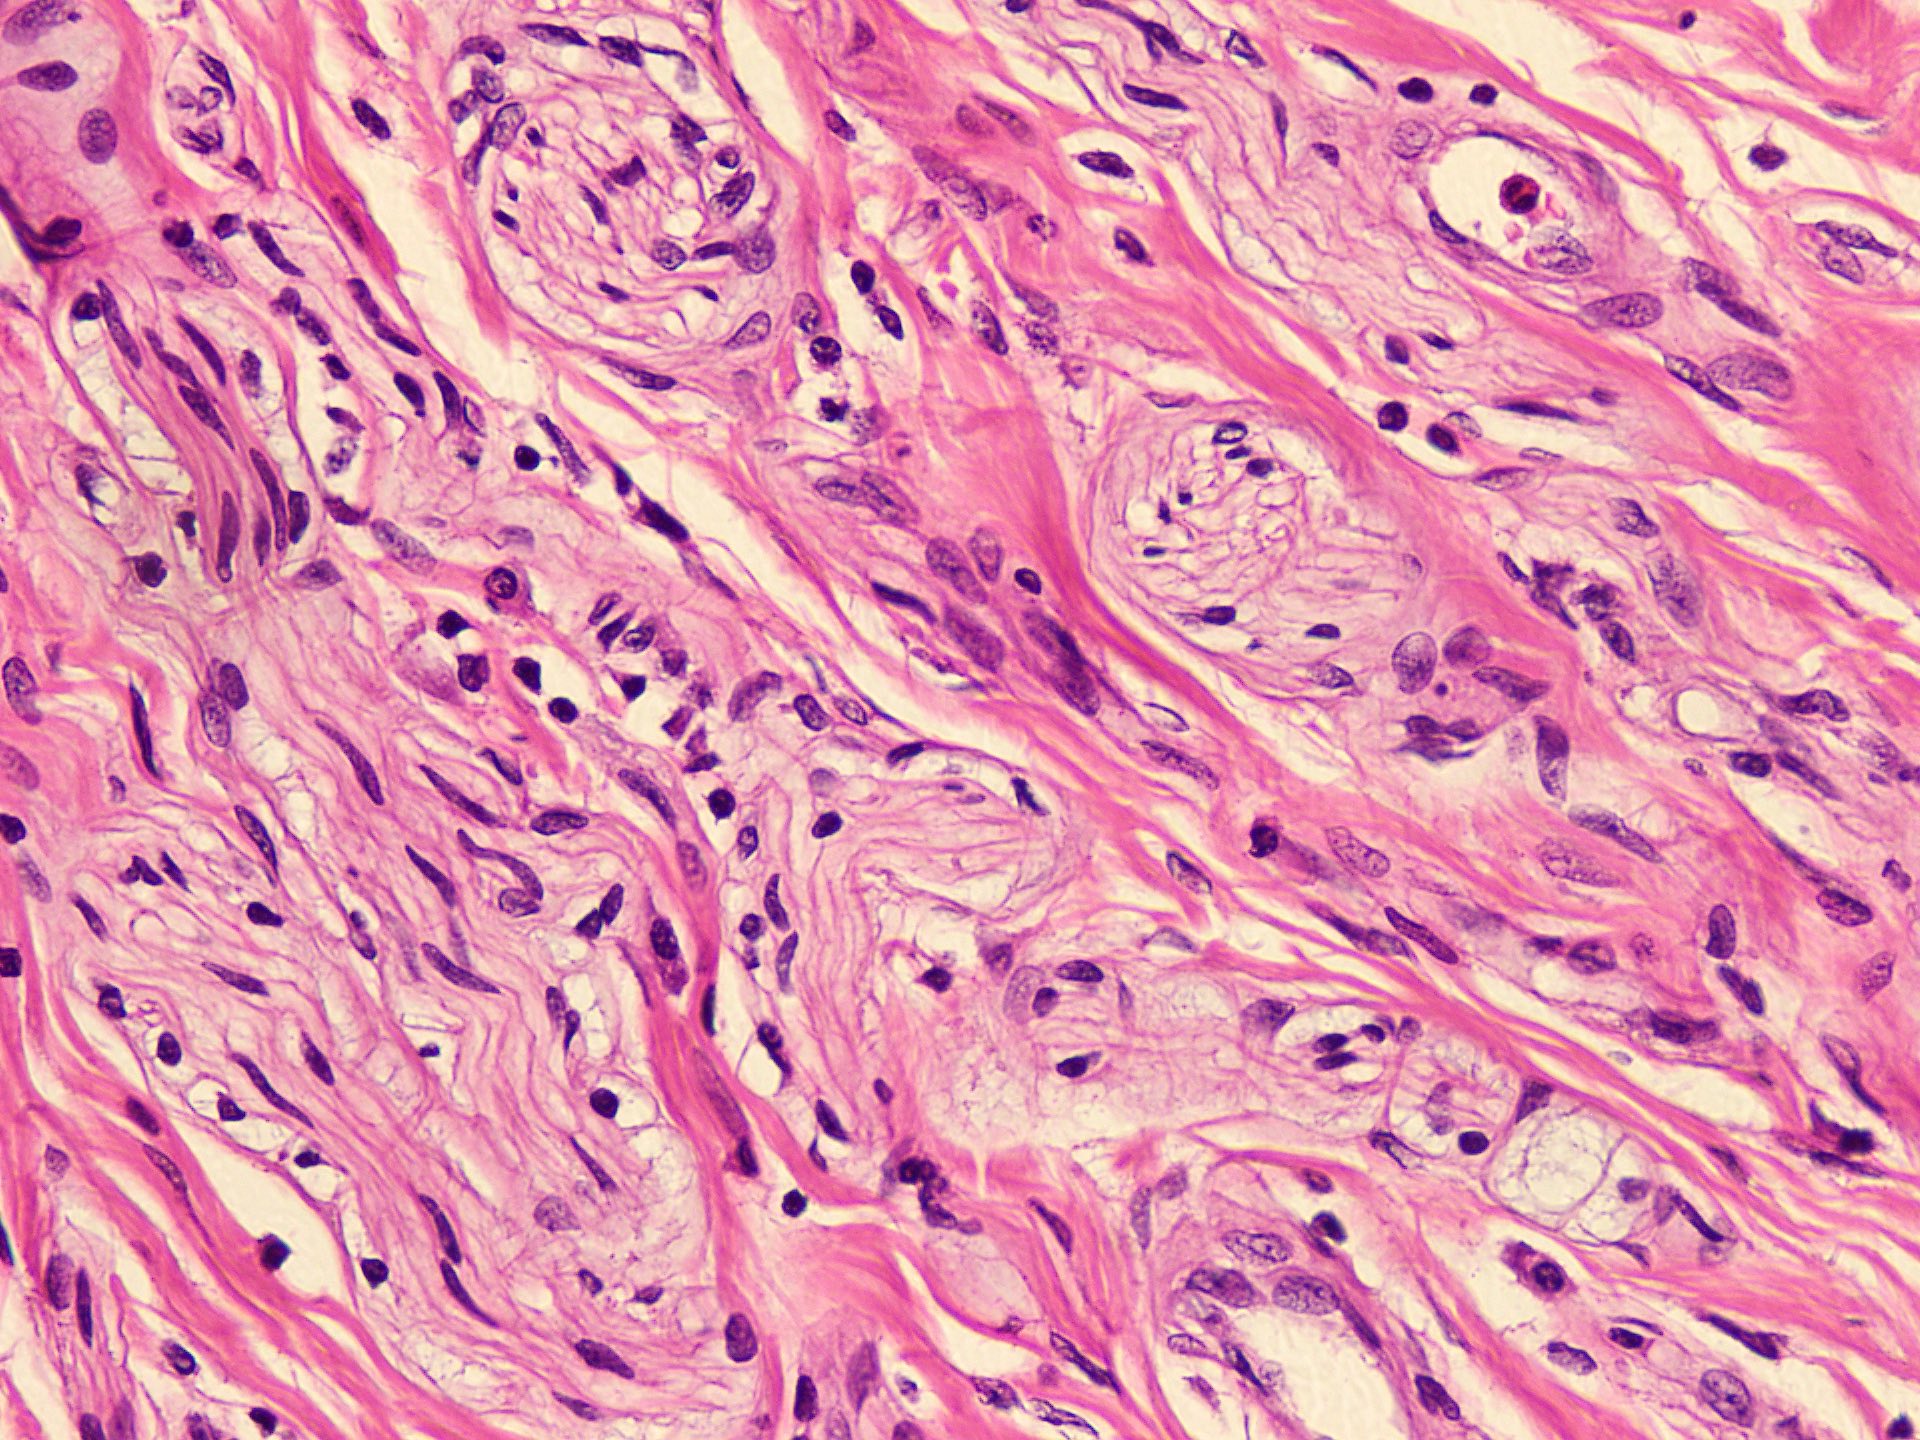

Microscopic (histologic) description

- Circumscribed, unencapsulated spindle cell proliferation arranged in short bundles comprised of axons, Schwann cells, endoneurial cells and perineurial cells (World J Clin Cases 2020;8:3821, Acta Biomed 2020;91:122, StatPearls: Neuroma [Accessed 21 September 2022])

- Peripheral palisading is not present (World J Clin Cases 2020;8:3821)

- Prominent scar tissue with dense collagen may be present (Acta Biomed 2020;91:122, StatPearls: Neuroma [Accessed 21 September 2022])

- Dystrophic calcifications are rarely present (Acta Biomed 2020;91:122)

Microscopic (histologic) images

- Microscopy: The sections examined show a circumscribed, unencapsulated lesion composed of variable sized, closely packed nerve bundle along with scar tissue in the background.

A patient presented with a painful nodule that developed after an amputation of the left first finger. On examination, the nodule is painful. Excision of the lesion is performed which shows the histology above. Which of the following is the most likely diagnosis?